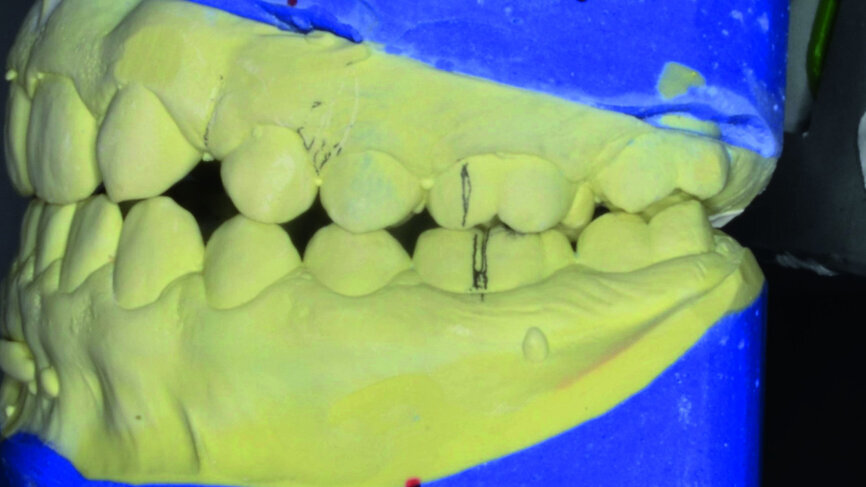

- Initial CR mounting (Figs. 19–21).

- Upper bracket placement (Fig. 22): level and align the gingival margins, and correct the torque on the upper canines who will substitute the lateral incisors.

- Implants space opening: substitute laterals with canines (Figs. 23–25) and substitute canines with first premolars (Figs. 26–28).